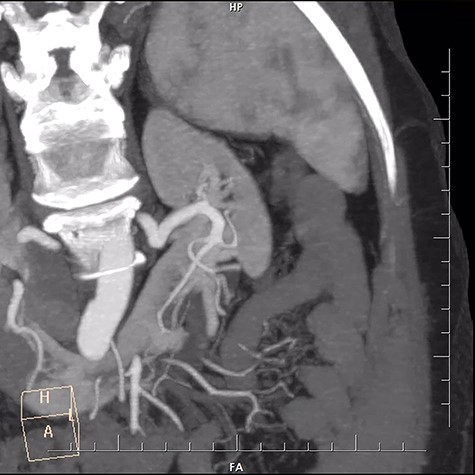

A 29-year-old female patient with end stage renal failure was our recipient. She was considered for a pre-emptive transplant and the only viable living donor was her 59-year-old mother. Upon evaluation for the donor, all the criteria were met except for the detected horseshoe kidney by CT scan. Dynamic CT revealed one renal artery and one renal vein for each side, a long but thin isthmus connecting lower poles with no visible arterial supply (Fig. 1). Sizes of the left and right kidneys were 110 × 38 cm and 117 × 42 cm, respectively. Absence of a connecting caliceal system was established with a descending urography. We did not perform a dynamic renal perfusion scintigraphy to assess the split functions of the kidneys since their sizes, respective vasculature and measured GFR values indicated sufficient capacity for each kidney. Left portion of the kidney was considered for nephrectomy.

With a left subcostal incision transperitoneal exploration was performed. The left kidney had indeed one renal artery and one renal vein. There were two ureters for the left kidney. The vessels, ureters were prepared and the kidney was mobilized up to the isthmus. A temporary bulldog clamp was put on left renal artery to determine the demarcation zone and it was shown to form around isthmus (Fig. 2). The artery and vein were divided and the isthmus separation was performed with a 60-mm Endo GIA Black stapler (Medtronic, USA) (Fig. 3). After separation, no bleeding and no urine leakage were detected from transacted surface of the remaining kidney.